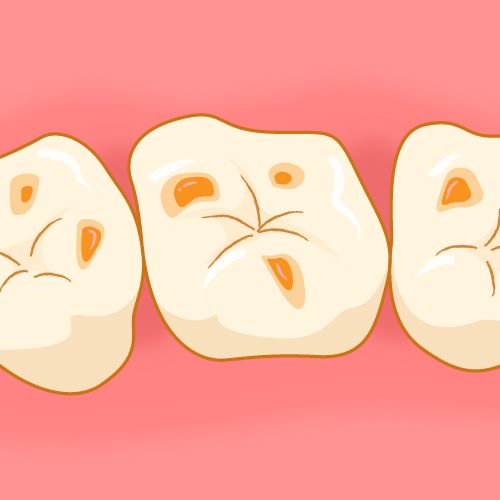

⑥ 前回詰めた綿花の状態を確認して、良い状態なら、「根管充填剤」(マスターポイント・アクセサリーポイント)というお薬を、余分な空間がないように根っこに詰めます。

⑥ 前回詰めた綿花の状態を確認して、良い状態なら、「根管充填剤」(マスターポイント・アクセサリーポイント)というお薬を、余分な空間がないように根っこに詰めます。 Q1.痛みはありますか?

Q1.痛みはありますか? ② 次に、「根管長測定器」という機械を使い、根っこの長さを正確に測ります。

② 次に、「根管長測定器」という機械を使い、根っこの長さを正確に測ります。

⑤ 次に、仮詰めをします。

⑤ 次に、仮詰めをします。 虫歯が神経まで達して炎症を起こしているので、人によってはズキズキとした痛みを感じる方もいます(>_<)

虫歯が神経まで達して炎症を起こしているので、人によってはズキズキとした痛みを感じる方もいます(>_<)